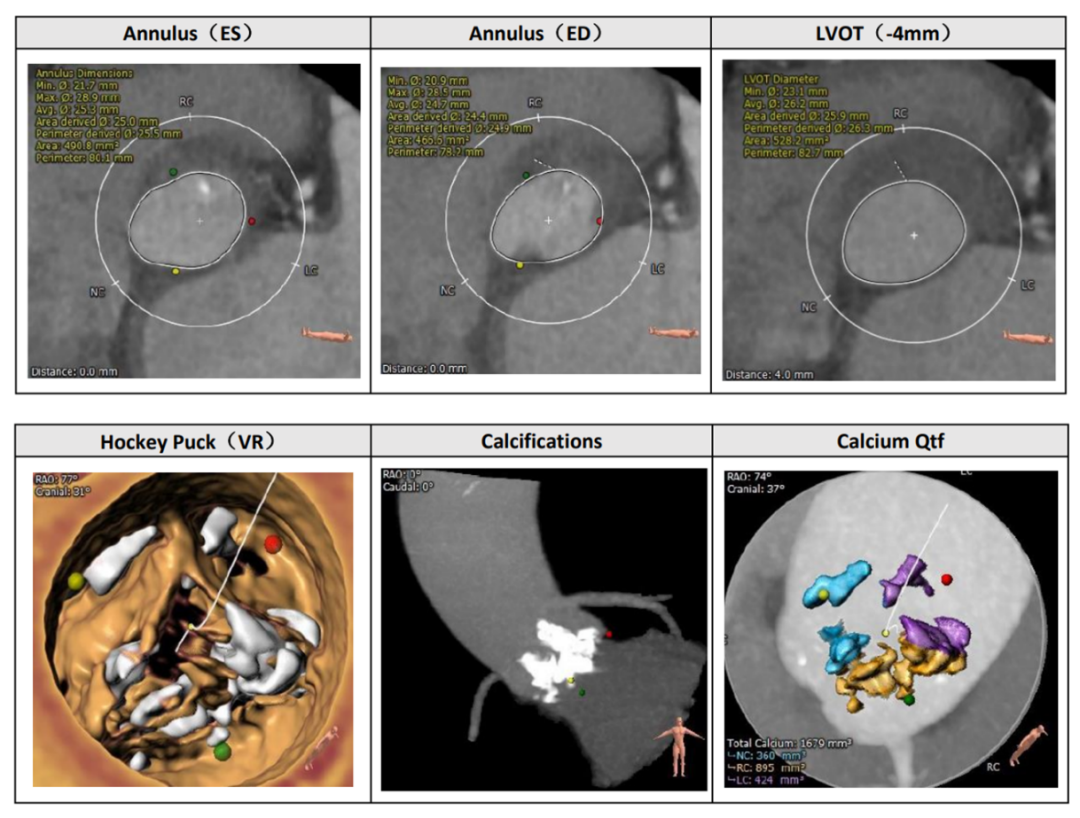

CT评估

主动脉瓣为Type I型二叶瓣,左右可见融合嵴,瓣环面积为 490.8mm²,钙化积分1679mm³左冠脉开口高度13.1mm,左冠瓣叶长度20.2mm,右冠开口高度15.9mm,右冠瓣叶长度20.6mm。

主动脉根部解剖